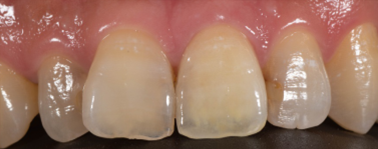

良くも悪くも人の印象を左右する前歯。

当院の歯科医師はその前歯の治療にとても神経を使います。

本来その人が持っていたであろう歯に近づくように細心の注意を払い治療しております。

| 治療期間 | 4週間 |

|---|---|

| 費用 | ジルコニアクラウン 15万4千円(顕微鏡治療の場合19万8千円) |